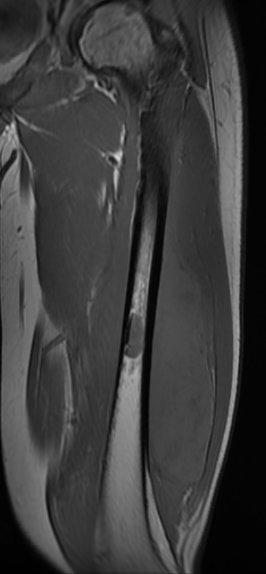

MRI

Low signal intensity of T1 / high signal intensity on T2

- intramedullary extent

- skip lesions

Significant soft tissue mass with significant edema

Pathological fracture with skip lesion

Ewing's distal femur